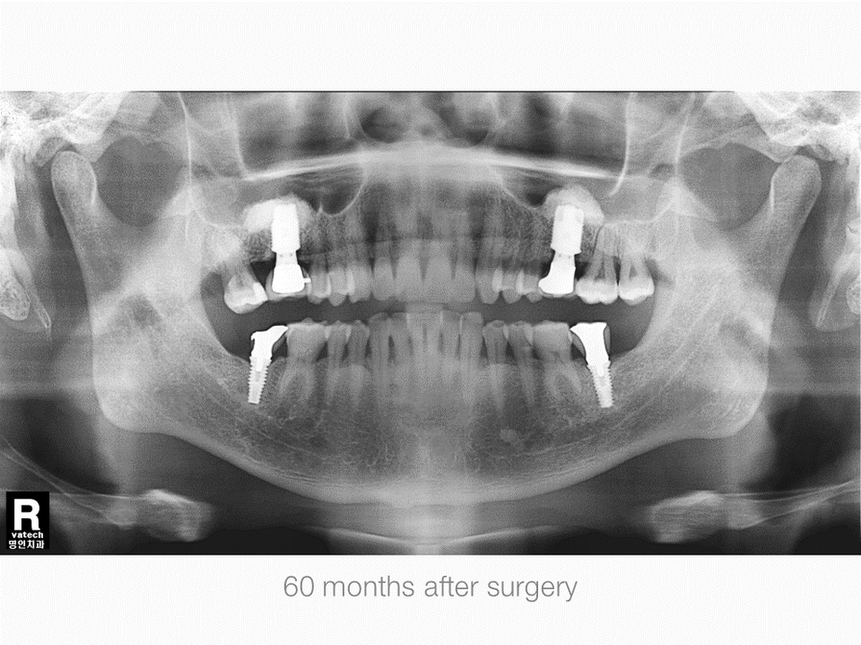

Right Maxillary, First Molar Area, Sinus & Crestal Augmentation

Gender: Male

Age: 53 years old

Operation Site: #16 Sinus Graft, Crestal Defect